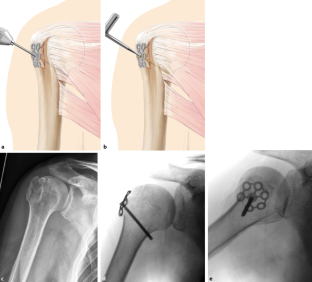

Operationstechnik

Darstellung der Tuberculum-majus-Fraktur über anterolateralen Deltoideus-Split. Reposition der Fraktur und passagere Retention durch Kirschner-Draht oder Kugelspieß oder Anschlingen der Supraspinatussehne und Retention nach distal. Manuelles Vorbiegen und Auflegen der Bamberger Platte und Fixierung mit konventionellen und/oder winkelstabilen Schrauben. Optionales Fixieren der Rotatorenmanschette an der Platte. Genaue Kontrolle der Implantatlage mit Bildverstärker zur Vermeidung einer unzureichenden Distalisierung des Tuberculum majus.

Exposure of the fracture of the greater tuberosity by an anterolateral approach. Open reduction and temporary retention with a Kirschner wire or a “Kugelspieß” or reinforcement of the supraspinatus tendon and distal retention. Bending and positioning of the Bamberg plate and fixation by conventional or locking screws. Optional fixation of the rotator cuff to the plate. Exact monitoring of the implant position using the image intensifier to avoid inadequate distalization of the greater tuberosity.

Abb. 1

Abb. 2a–c

Abb. 3a–c